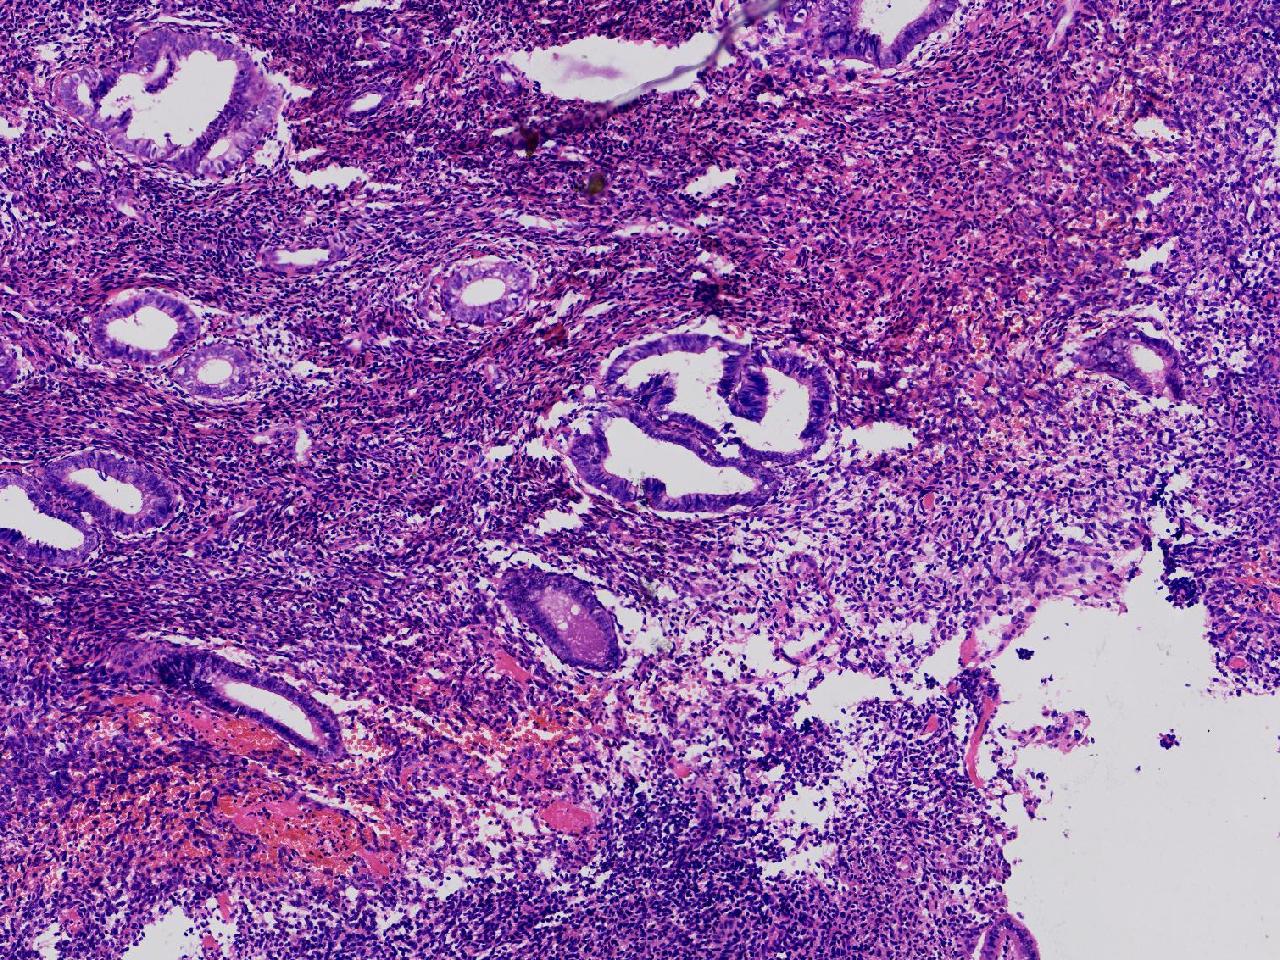

请教诊断。局灶够不够非典?

性别

女

年龄

44岁

阴道不规则出血20余日,彩超示:内膜线居中,厚15毫米。

子宫内膜

灰粉色不整形软组织多块,3X2X1厘米。

不够非典

有输卵管上皮化生,感觉不够非典。